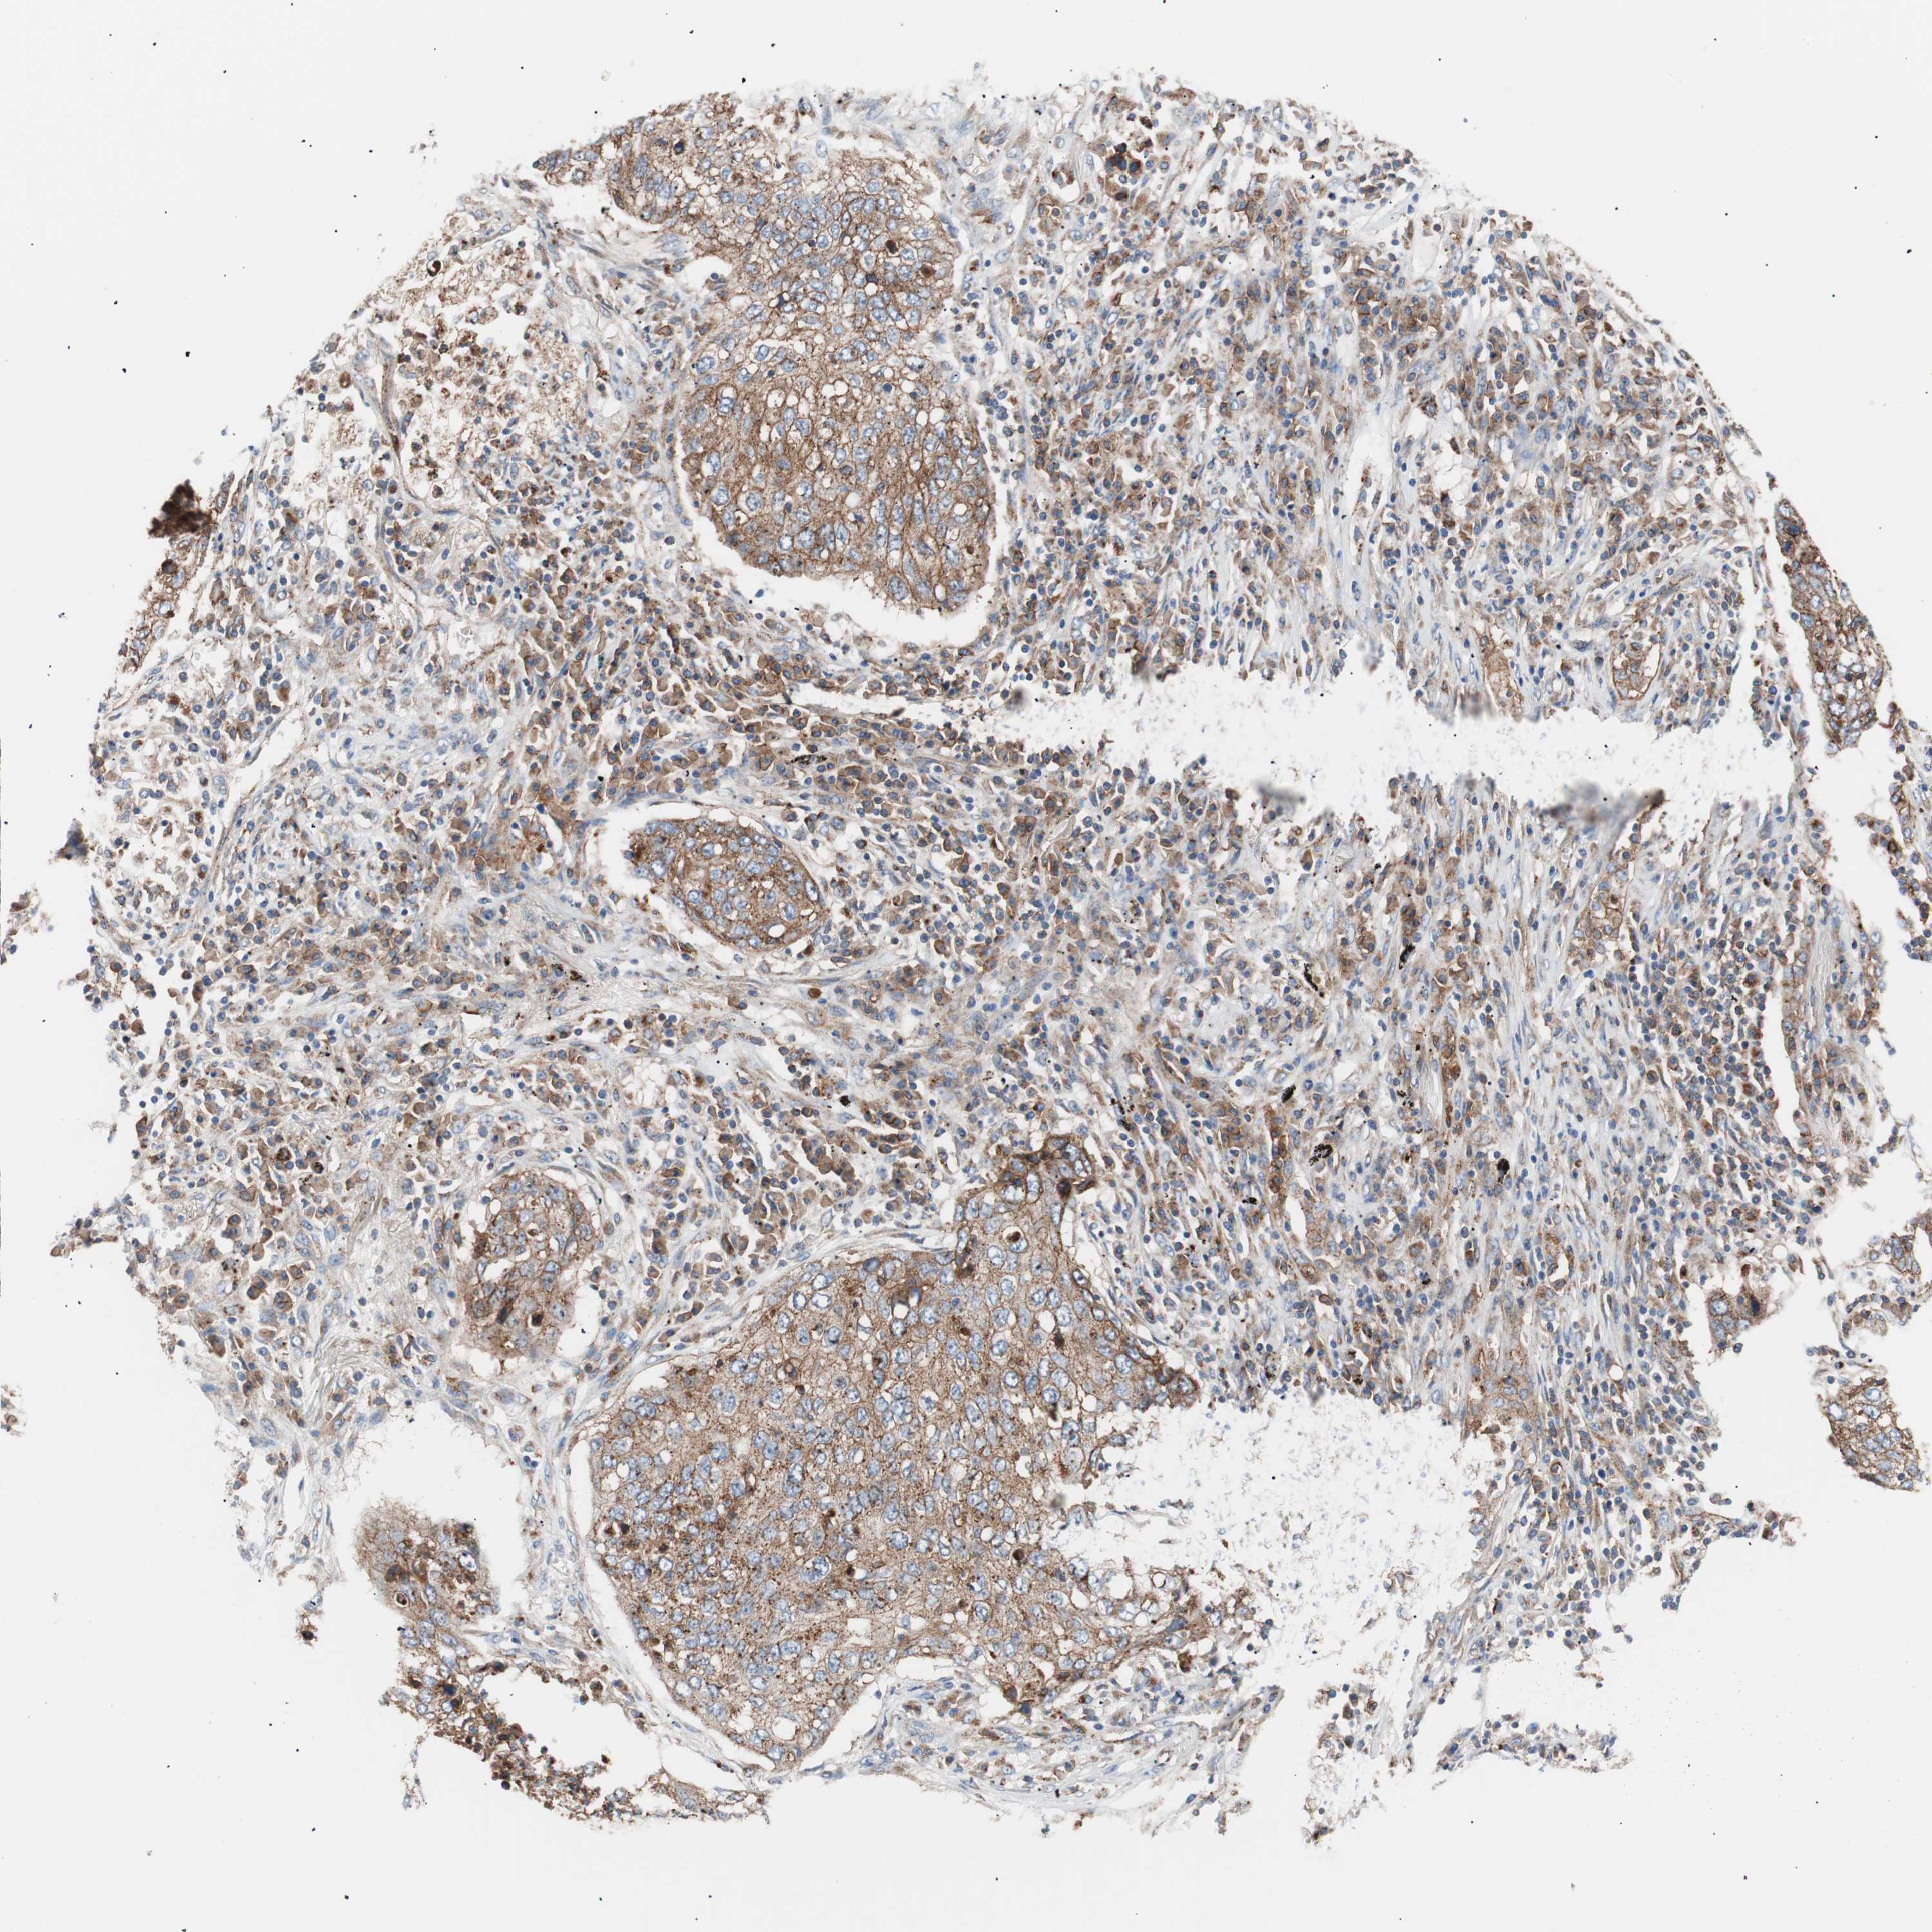

LUNG SQUAMOUS CELL CARCINOMA (TCGA) - Interactive survival scatter ploti

The Survival Scatter plot shows the clinical status (i.e. dead or alive) for all individuals in the patient cohort, based on the same data that underlies the corresponding Kaplan-Meier plots. Patients that are alive at last time for follow-up are shown in blue and patients who have died during the study are shown in red.

The x-axis shows the expression levels (FPKM) of the investigated gene in the tumor tissue at the time of diagnosis. The y-axis shows the follow-up time after diagnosis (years). Both axes are complimented with kernel density curves demonstrating the data density over the axes. The top density plot shows the expression levels (FPKM) distribution among dead (red) and alive patients (blue). The right density plot shows the data density of the survived years of dead patients with high and low expression levels respectively, stratified using the cutoff indicated by the vertical dashed line through the Survival Scatter plot. This cutoff is automatically defined based on the FPKM cutoff that minimizes the p-score. The cutoff can be changed by dragging the vertical line or by entering a cutoff value in the square labeled "Current cut-off".

Under the Survival Scatter plot the p-score landscape (black curve; left axis) is shown together with dead median separation (red curve; right axis). Dead median separation is the difference in median mRNA expression between patients who have died with high and low expression, respectively. It is calculated as follows: median FPKM expression of dead patients with high expression - median FPKM expression of dead patients with low expression. This is intended to aid the user in visually exploring custom cutoffs and the associated p-scores and dead median separation.

Individual patient data is displayed and can be filtered by clicking on one or more of the category buttons on the top of the page. Categories describing expression level and patient information include: high, low, alive, dead, female, male and tumor stages. The scale of the x-axis can be toggled between linear and log-scale by clicking on the "x log" button. Mouse-over function shows TCGA ID, patient information and mRNA expression (FPKM) for each patient.

& Survival analysisi

Kaplan-Meier plots summarize results from analysis of correlation between mRNA expression level and patient survival. Patients were divided based on level of expression into one of the two groups "low" (under cut off) or "high" (over cut off). X-axis shows time for survival (years) and y-axis shows the probability of survival, where 1.0 corresponds to 100 percent.

FLOT2 is not prognostic in Lung Squamous Cell Carcinoma (TCGA)

: 80.87

: N/A

N/A

Average pTPM 82.6

Number of samples 489